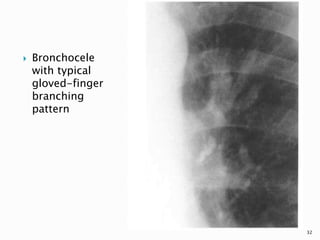

 Other, less frequently seen manifestations

of a central tumour include mucoid

impaction, air trapping, and pulmonary

vascular occlusion or reflex vasoconstriction

leading to oligemia or infarction

 Bronchocele

with typical

gloved-finger

branching

pattern

32